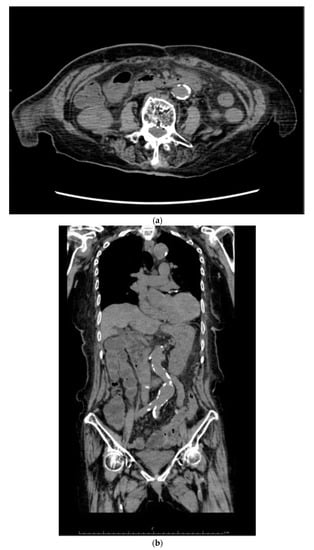

Her past history included colonic perforation, abdominal wall hernia with strangulated ileus, and resection of about 2 m 30 cm (59.1 inches) of the terminal ileum (Figure 1). Five years prior to this admission, she was diagnosed with strangulated ileus, and the small intestine was resected, 7 cm from the terminal ileum and 50 cm from the ligament of Treitz (Figure 2). At presentation, the patient’s blood pressure was 95/67 mmHg, heart rate was 59 beats per minute, SpO2 as 95%, and her temperature was 36.6 °C. On physical examination, normal breath sounds and heart sounds with mild systolic murmurs were observed. The abdomen was flat and soft. Murphy’s sign was negative, and there was no costovertebral angle tenderness. Lower leg oedema was observed. The results of blood tests were as follows: white blood cell count 15.30 × 103/μ (neutrophils 78.3%, lymphocytes 15.5%, monocytes 5.6%, eosinophils 0.4%, basophils 0.2%), red blood cell count 3.34 × 106/μ, hemoglobin 11.3 g/dL, hematocrit 33.2%, platelet count 27.9 × 104/μ, total bilirubin 1.6 mg/dL, aspartate aminotransferase (serum glutamic-oxaloacetic transaminase) 48 IU/L, alanine aminotransferase (serum glutamic-pyruvic transaminase) 37 IU/L, total protein 5.2 g/dL, albumin 2.5 g/dL, blood urea nitrogen 18.7 mg/dL, creatine 1.13 mg/dL, Na 143 mEq/L, K 1.7 mEq/L, Cl 99 mEq/L, Ca 5.0 mg/dL, P 2.8 mg/dL, Mg 0.8 mg/dL, and estimated glomerular filtration rate 34.1 mL/min/L. An abdominal computed tomography showed mild oedema of the colon, and no other obvious abnormalities (Figure 3). No obvious organic abnormalities were noted on imaging, but the bowel was shortened because of repeated bowel resections. Colonic specimens showed only nonspecific inflammatory findings (Figure 4a,b). We believe that this inflammatory finding was due to an imbalance between the protective and aggressive factors of the intestinal tract due to ageing.

Figure 3. Findings from the abdominal computed tomography scan. Most of small intestine lacked in (a,b).